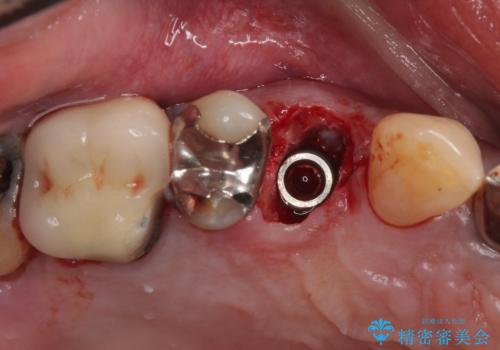

当院での根管治療および歯周外科治療を併用した保存療法、並びに1DAYインプラントによる短期間インプラント治療の双方をご説明し、即日でインプラント治療を選択されました。

仮歯を用意した上で、抜歯即時埋入・即時荷重インプラントによる補綴治療を行うこととしました。

従来のインプラント治療について回った3回の外科手術や半年移動の治療期間とは無縁の、短期間治療を達成することができました。